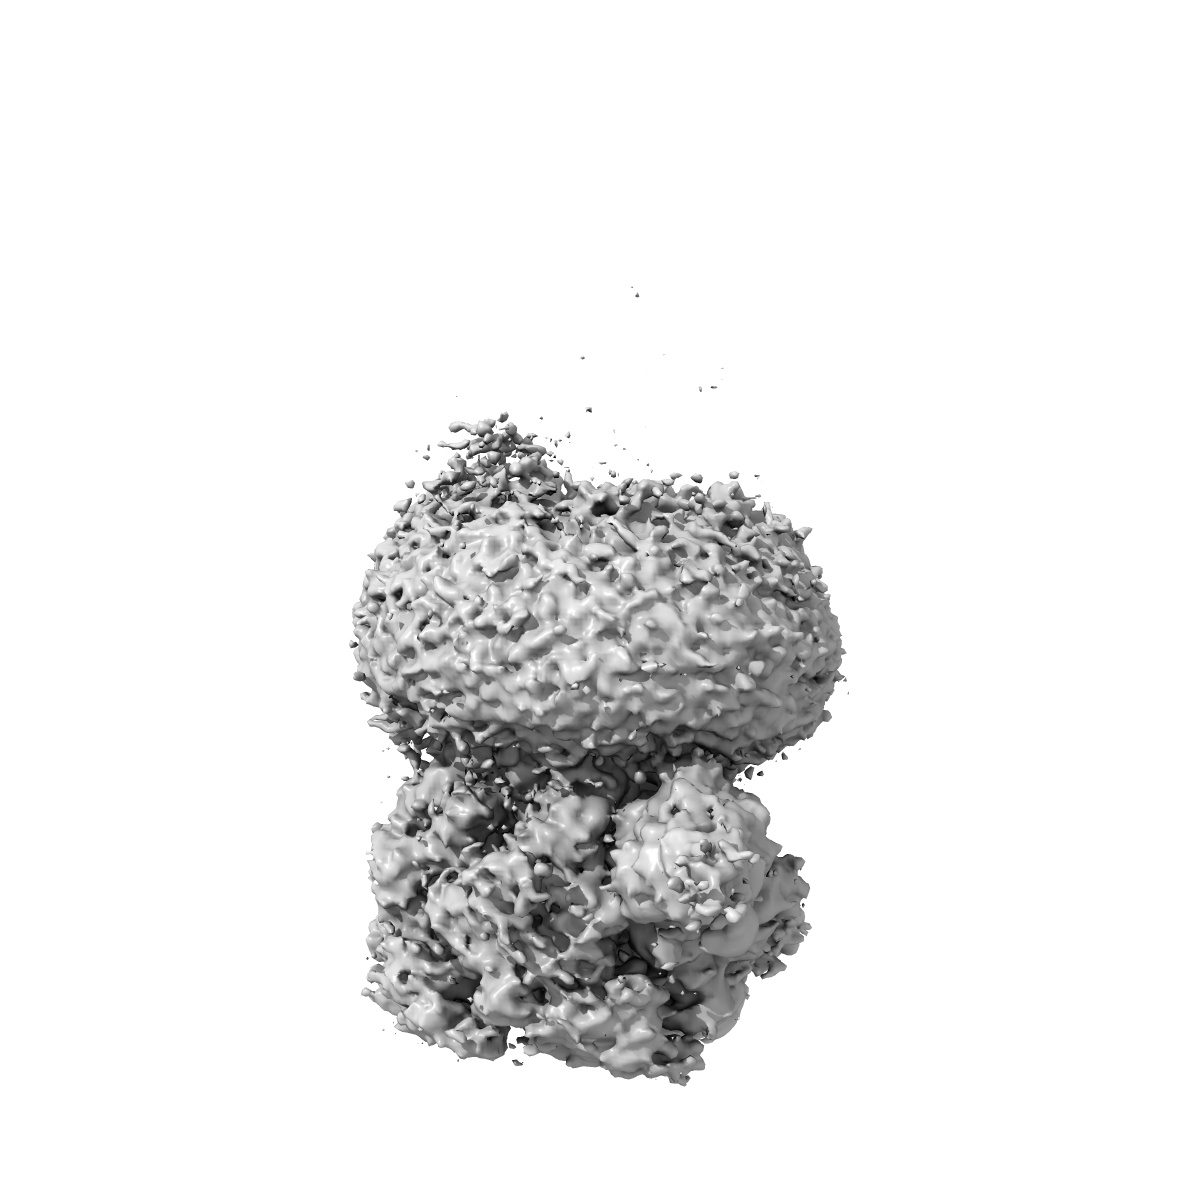

Cryo-EM structure of human full-length beta3gamma2 GABA(A)R in complex with GABA and nanobody Nb25

Single-particle3.1 Å

Sample: Human full-length beta3gamma2 GABA(A)R in complex with GABA and Nanobody Nb25

Differential assembly diversifies GABA A receptor structures and signalling.